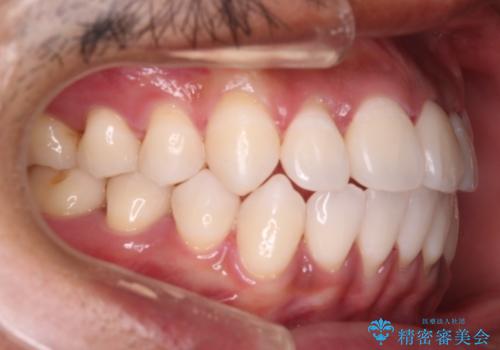

開口(オープンバイト)のため噛み合わせを考慮してワイヤー矯正を提案させていただきました。

IPR(歯と歯の間を削る処置)と顎間ゴムを行い歯並びを整える治療計画を立てました。

早く終わらせたいとの事でしたが、ゴム掛けを頑張っていただいたので

9ヶ月という短い期間で治療が完了しました。